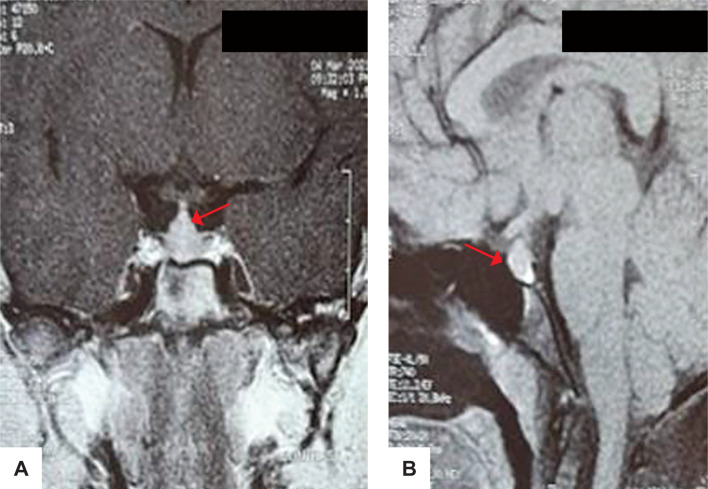

Primary growth hormone (GH) resistance or growth hormone insensitivity syndrome, also called Laron syndrome, is a hereditary disease caused by mutations in the GH receptor or in the post-receptor signaling pathway. This disorder is characterized by postnatal growth failure resembling GH deficiency. Differentiating the two conditions is necessary. We present the cases of two siblings, a 16-year-old female and a 9-year-old male, born from a consanguineous union. Both had normal birth weights with subsequent severe short stature and delayed teeth eruption, with no features suggestive of any systemic illness. Serum insulin-like growth factor 1 (IGF1) and insulin-like growth factor binding protein 3 (IGFBP3) were both low. Suspecting GH deficiency, provocative testing with clonidine was done revealing peak growth hormone >40 ng/mL in both patients. In view of low IGF1 and IGFBP3 and high GH on stimulation, IGF1 generation test was done for both siblings, with values supporting the diagnosis of GH insensitivity or Laron syndrome.